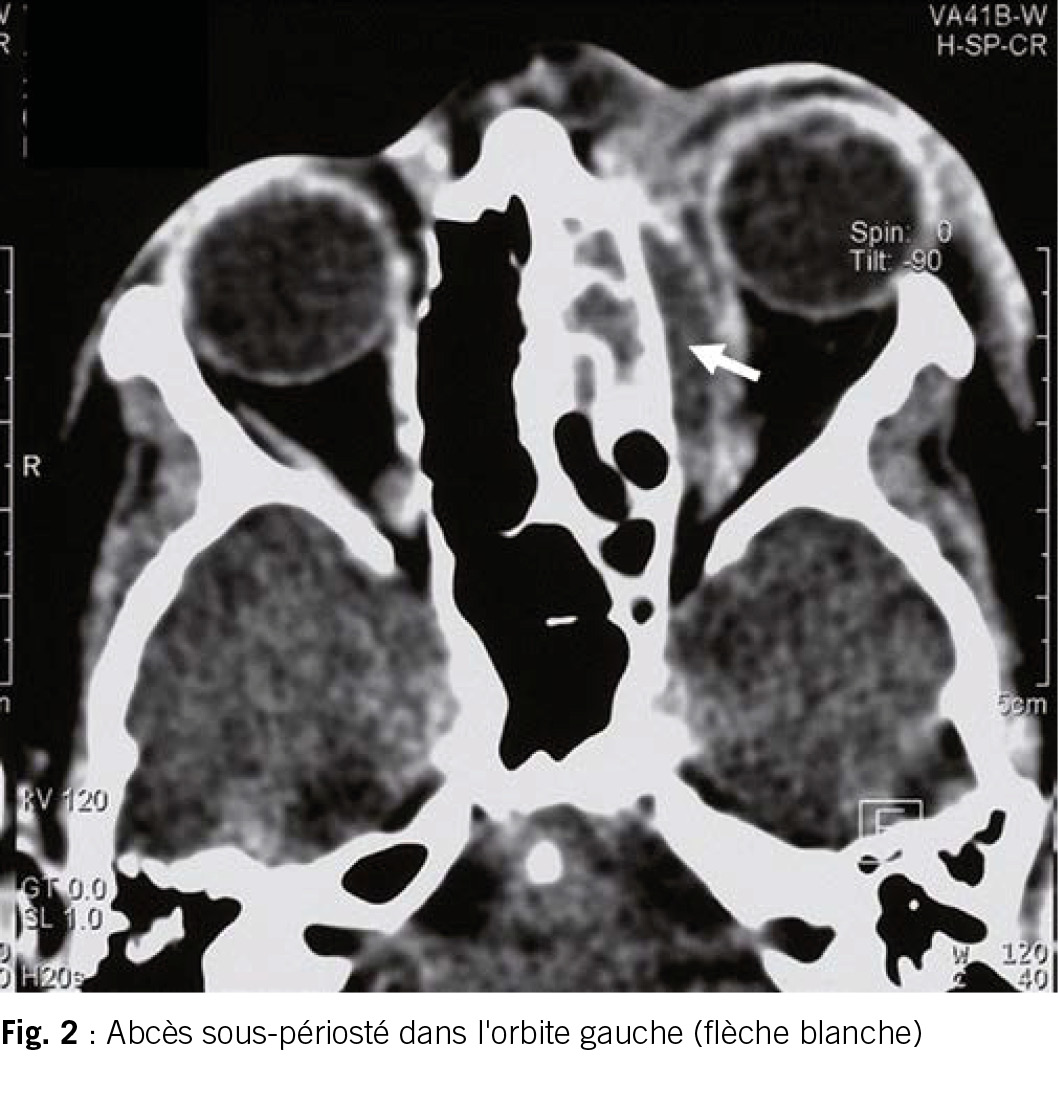

L’enfant dans ce cas ne peut toutefois plus ouvrir activement l’œil et présente des mouvements oculaires douloureux, ce qui plaide en faveur d’une complication orbitaire pertinente. Et c’est ainsi que la suite de l’examen d’urgence à l’hôpital révèle au scanner un gros abcès sous-périosté dans l’orbite gauche (fig. 2). L’abcès est soulagé chirurgicalement et traité par antibiotiques. Une lésion permanente de l’œil peut être évitée.

Les complications d’une rhinosinusite bactérienne aiguë peuvent survenir aussi bien chez l’enfant que chez l’adulte. Chez l’enfant, ce sont surtout les complications orbitaires qui se produisent, à partir des sinus ethmoïdaux. Les bactéries traversent alors la lame papyracée et pénètrent dans l’orbite. Ensuite, l’abcès sous-périosté se forme par décollement de la périorbite. En l’absence de traitement, les complications orbitaires peuvent entraîner une cécité ou une infection ascendante potentiellement mortelle avec thrombose du sinus caverneux et méningite.